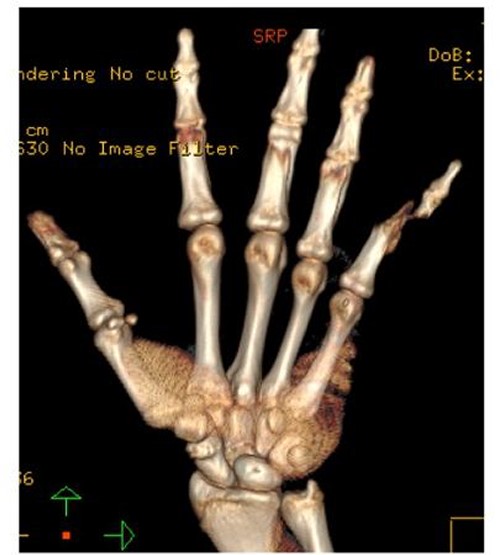

A 15-year-old boy, right handed, was not known to have any chronic medical illnesses. He presented to the emergency department (ED) with a history of severe left-wrist pain and swelling after falling from a height of 5–6 meters on an outstretched hand with the wrist in extension three hours prior to the ED presentation. The pain is mainly located in the left wrist’s dorsum and distal part of the forearm. Increasing pain with movement and relived with immobility. On examination, a normal-appearing wrist. No open wounds or lacerations, nor abrasions. There is no obvious deformity. There was mild swelling in the wrist. Tenderness over the dorsal radial wrist, including the anatomical snuff box. The range of motion was restricted due to pain. The neurovascular examination was normal. A plain radiograph in the ED showed a scaphoid tubercle fracture and a capital bone fracture. Initial radiographs are shown in Fig. 1). The patient was taken for computerized tomography (CT) to better define the extent of the injury (Fig. 2). A CT scan showed a displaced fracture of the capitate carpal bone, with an avulsion fracture at the distal tubercle of the scaphoid carpal bone, with extension to the articular surface. In addition to perilunate fracture, the rest of the carpal bone’s alignment is maintained. The patient was shifted to the operating room for open reduction and k-wire fixation of the scaphoid and capitate fracture of the left hand. Under general anesthesia, a tourniquet was applied. The incision was over the dorsal aspect of the left wrist, proceeding with the wrist capsule opening. The fracture was fixated with two Kirschner wires. Alignment was assured intraoperatively with an x-ray (Fig. 3). Plain radiographs post-fixation showed intact alignment. Postoperatively, the wrist was immobilized in a long-arm splint. The Kirschner wires and the protected splint were removed at 5 and 8 weeks, respectively. Immediately afterward, physiotherapy started. A few months following surgery, the site of the fracture healed radiologically. The patient had no pain, and the range of motion was acceptable after a period of physiotherapy. Figure 4 demonstrates a medical illustration of a scaphocapitate fracture.